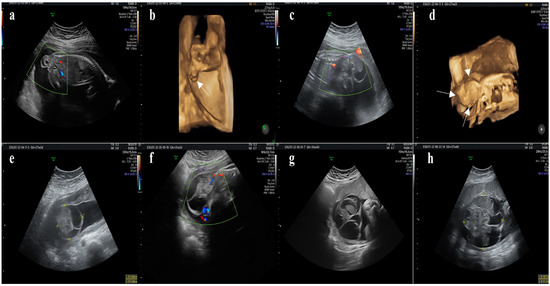

| Abdominal ultrasound | 21st week |

|

| Abdominal ultrasound | 29th week |